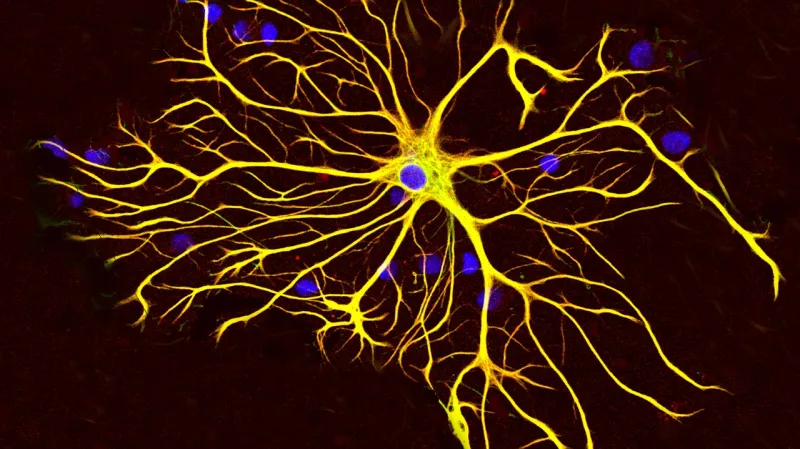

Gliomy jsou mozkové nádory, které často vznikají v nervových kmenových buňkách. Zralejší typy mozkových buněk, jako jsou astrocyty, věda považovala za méně náchylné ke vzniku nádorů. Nedávné poznatky ale ukázaly, že po poranění mohou astrocyty opět vykazovat chování kmenových buněk.

Astrocyty za normálních okolností připomínají hvězdy – ostatně proto také dostaly své jméno. „Ale bez p53 a po poranění stáhly své větve a více se zakulatily,“ popsala profesorka Parrinellová. Nebyly pak podle ní sice úplně podobné kmenovým buňkám, ale jednoznačně se změnily.

„Nechali jsme tedy myši zestárnout, pak jsme se na buňky podívali znovu a zjistili jsme, že se astrocyty vrátily do stavu podobného kmenovým buňkám, včetně stop spojených s ranými gliomovými buňkami, které se mohou dělit,“ doplnila.